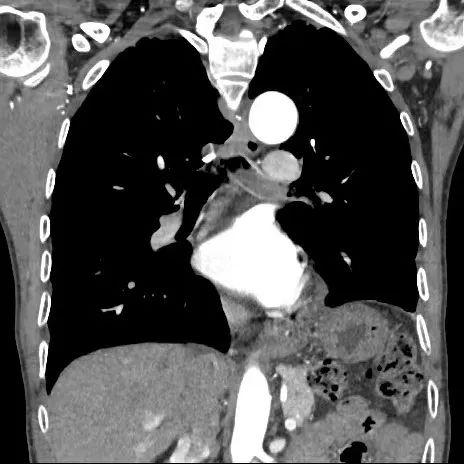

两周后,吴某如约再次入院,按照计划择期安排了支气管镜介入治疗。但这次住院后,医生发现吴大爷的气短症状又较半个月前加重了,稍微活动后就有窒息感,在吸氧3L/min的情况下,指脉氧仅仅维持在90%的临界线上。而陈晖副主任医师查房中发现,吴某呈典型的喘息貌,左肺呼吸音完全消失,并且胸部CT影像中,左主支气管已经被新生物完全堵塞,左肺下叶已完全不张。

左主支气管几乎完全堵塞

肿物向右侧侵犯

术中,陈晖发现患者的左主支气管新生物已经将管腔堵塞得严严实实,距上一次住院短短两周的时间里,肿物明显迅速生长了很多。镜下直观到的情景更严峻、更不容乐观,巨大的新生物已经向右侧侵犯,随时可能将右主支气管也堵住。